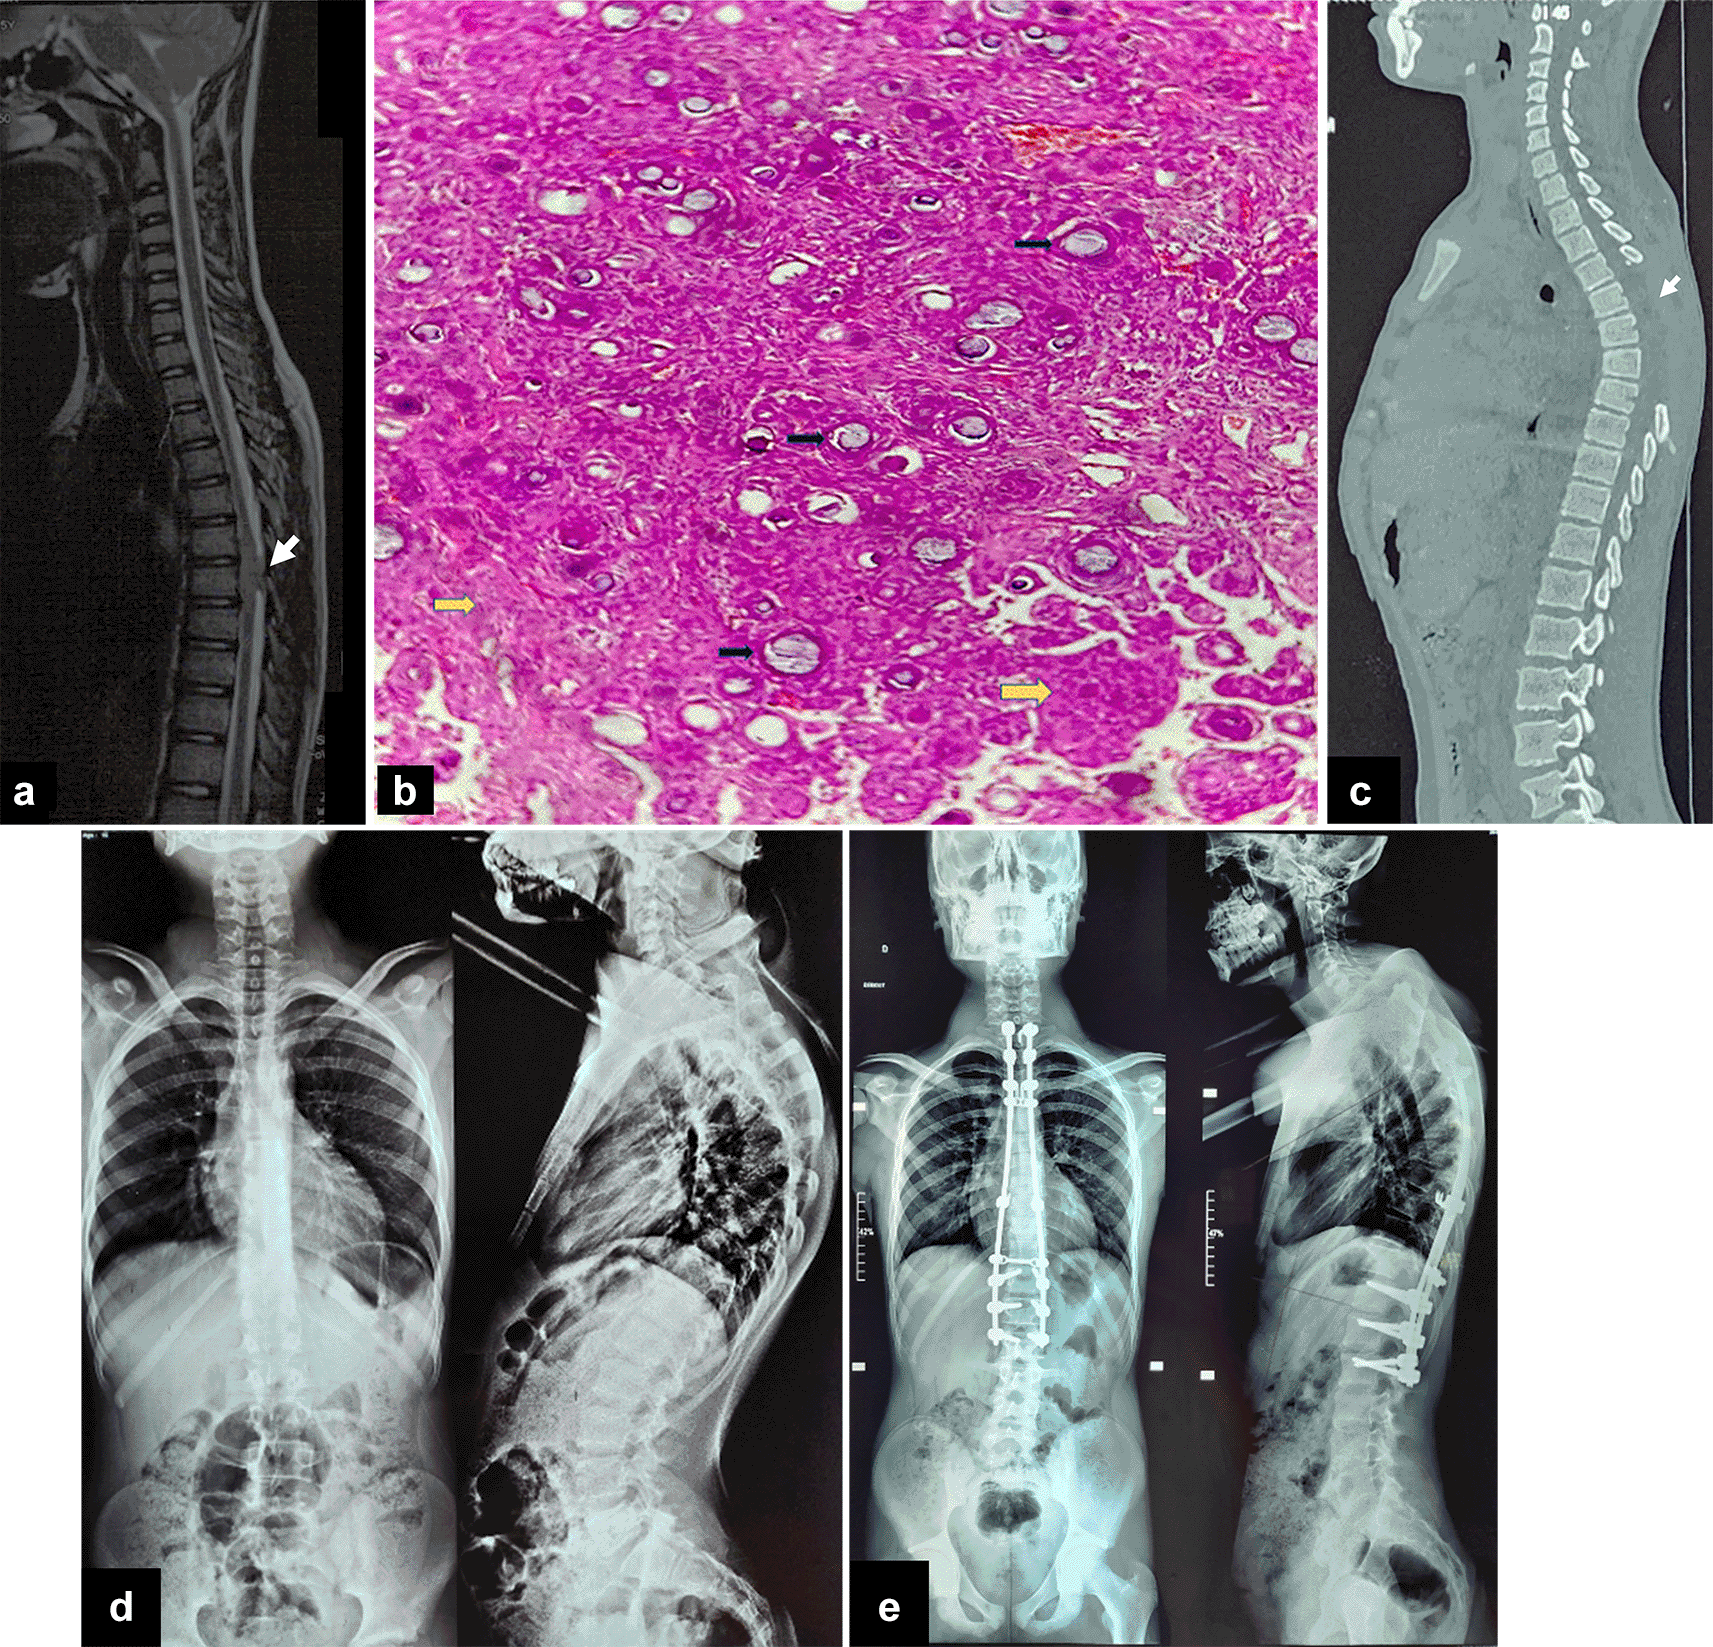

Given the presence of neurological signs, a spine MRI was performed showing a posterior intradural mass at the T6 and T7 vertebral levels, characterized by an extramedullary, well-circumscribed, homogeneous, and lobulated appearance. The lesion measured approximately 1.8 × 1.2 × 0.9 cm and exhibited iso-intensity on T1-weighted images and hyperintensity on T2-weighted images, with homogeneous and marked enhancement after contrast administration. The mass exerted a local mass effect, resulting in dorsal spinal cord compression. These findings were initially suggestive of a thoracic glioma, with differential diagnoses including low-grade ependymoma or astrocytoma [Figure 1a, 1c].

Histopathological examination revealed a proliferation of meningothelial cells with poorly defined cytoplasmic borders, creating a syncytial appearance and exhibiting cytological pleomorphism. Numerous psammoma bodies were observed throughout the specimen, with no evidence of anaplasia or tumor necrosis [Figure 1b]. These findings were consistent with a WHO Grade 1 psammomatous meningioma.

Unfortunately, the postoperative course was complicated by the onset of hyperalgesic back pain two months later, along with the development of dorsal hyperkyphosis [Figure 1d]. This complication was attributed to the extensive laminectomy. A posterior thoracic arthrodesis was performed [Figure 1e]. The patient is currently undergoing motor rehabilitation with favorable clinical progress.